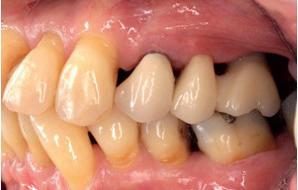

Esthetiek in de tandheelkunde, met name in het front, is een samenspel tussen de roze zachte weefsels en de witte harde weefsels. In het Engels wordt dit ook wel aangeduid met “pink and white esthetics”, waarbij het verkrijgen van correcte pink esthetics over het algemeen een grotere uitdaging vormt dan de white esthetics. Deze roze esthetiek is vooral van belang bij gebitselementen waarbij sprake is van recessie (het terugtrekken van de gingivalijn, waardoor de radix en een langere tand zichtbaar worden). De situatie wordt nog uitdagender wanneer een tand of kies niet is aangelegd, of in het verleden is verwijderd. Het element zorgt er immers voor dat de gingiva rondom de natuurlijke kroon ligt en dat er voldoende weefseldikte rondom deze kroon aanwezig is. Als het element ontbreekt, groeit het alveolaire bot dicht, omdat er geen radix meer is, en daarmee ook de mucosa (wanneer er geen element meer aanwezig is, spreken we niet meer van gingiva maar van mucosa), die dan afgevlakt is. De papillen tussen de afwezige elementen vlakken dan ook af.

Om één of meer afwezige elementen te herstellen bij een vaste voorziening, kan er een etsbrug of kunnen er implantaten worden geplaatst. De esthetiek valt of staat hierbij met de aanvulling van de zachte weefsels, zowel in de vorm van verbreding hiervan als het creëren van een zogenoemd emergence profile –dat wil zeggen dat de tand op een natuurlijk ogende wijze vanuit het tandvlees tevoorschijn moet komen.

Op 16-jarige leeftijd werd de patiënt door haar behandelend orthodontist naar de auteur verwezen voor een restauratieve oplossing voor de afwezige 11 en 21. In de tussenliggende periode had patiënt een retainer gedragen met twee kunststof tanden (afbeelding 1). Zowel de patiënt als haar moeder hadden een sterke voorkeur voor een implantaat gedragen vaste oplossing. Gezien haar jonge leeftijd was dit echter nog geen optie, omdat er nog verticale groei te verwachten viel. Implanteren op jonge leeftijd – dat wil zeggen vóór het 21e levensjaar – kan resulteren in een infrapositie van het implantaat, omdat de rest van het gebit nog verticaal kan doorgroeien.

Middels shared decision making werd het volgende plan overeengekomen: eerst zou er een etsbrug met vleugels op de 12 en 22 worden vervaardigd, om op 21-jarige leeftijd verder te gaan met implantologie.

Bij klinisch en röntgenologisch onderzoek viel echter op dat radix van de 12 en 22 een convergerende (de radices staan dan naar mesiaal en naar elkaar toe) in plaats van divergerende (radices staan dan van elkaar af) stand had. Door deze convergerende stand van de radices was er in mesio-distale zin geen ruimte voor twee implantaten ter plaatse van de 11 en 21. Er werd daarom besloten, in tegenzin

1. Retainer met twee frontelementen

2. OPT radices 12 en 22 convergeren

3. Vaste apparatuur voor torque 12 en 22

4. OPT radices 12 en 22 divergeren na orthodontische behandeling

van de patiënt, om eerst weer vaste apparatuur terug te plaatsen om de radices in een divergerende stand te plaatsen. Gelukkig verliep deze behandeling voorspoedig. (afbeelding 2 -4). Het volgende behandelplan werd gemaakt:

5. Beginsituatie voor behandeling